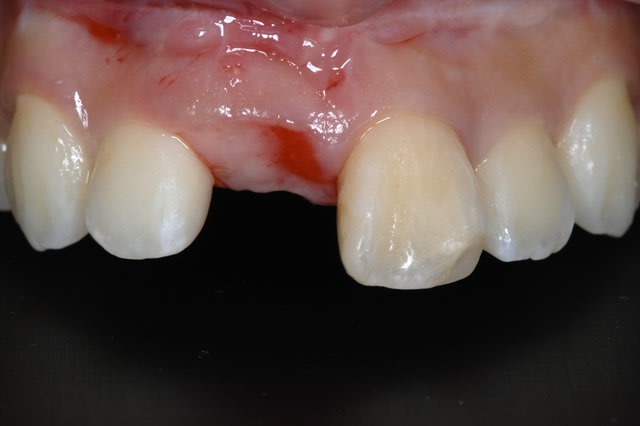

Manque d'os en vestibulaire, non ?

J'ai rarement eu des crêtes aussi belles en antérieur.

Je gonflerai en vestibulaire avec la technique du rouleau